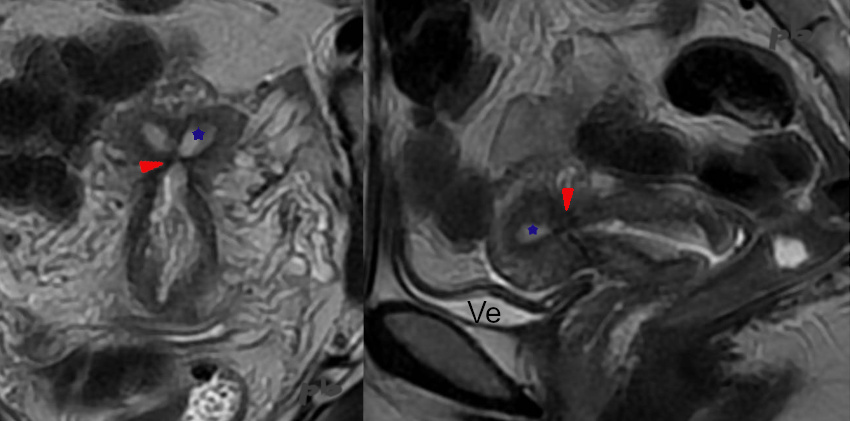

IRM coupes frontale et sagittale T2 de l’utérus.

Contexte initial d’hémorragie du post-partum traitée par embolisation utérine.

Synéchie (►) en hyposignal T2, fermant la cavité.

Endomètre (★)

Ve = vessie